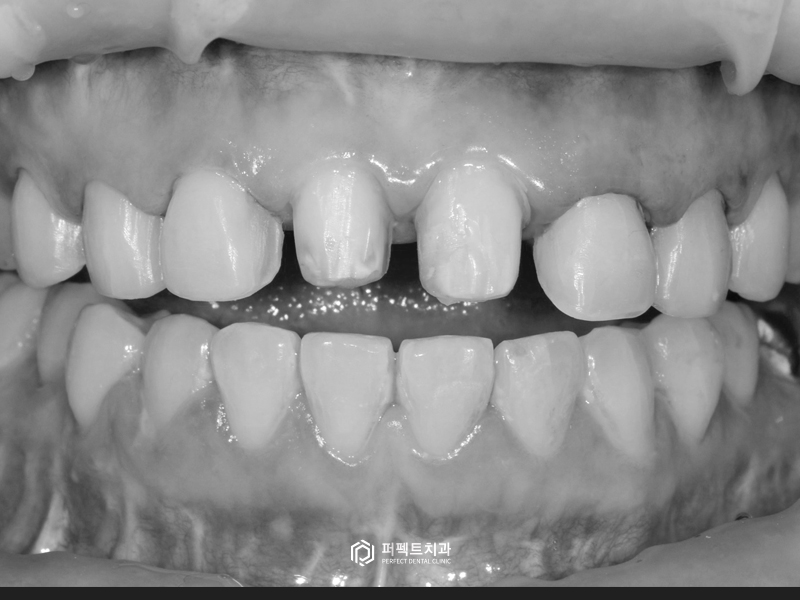

초진 사진을 보시면 중절치라고 하는 앞니 두 개가 크라운으로 씌워져 있는 상태입니다. 크라운이란 말 그대로 치아 전체를 뒤집어 씌우는 치료입니다.

치아를 씌운지 오래 됐고, 크라운이 어둡다고 느끼셔서 전체적으로 8개 치아를 하얗고 가지런하게 하고싶어 하셨습니다.

기존 크라운을 교체하기 위해 벗겨내야 하는데, 보통 크라운을 벗겨내면 놀래시는 분들이 많이 있습니다. 그 이유는 치아가 많이 깎여있기 때문인데요. 크라운을 씌우게 되면 자연스럽게 치아 삭제량이 많아질 수밖에 없습니다.

이처럼 크라운은 이미 치아가 많이 삭제된 상태이기 때문에 크라운보다 치아삭제량이 적은 라미네이트로 시술을 할 수 없습니다. 옆에 있는 치아들은 아직 치료를 하지 않은 상태이기 때문에 최소삭제 폴리네이트와 잇몸성형을 진행하기로 하였습니다.

말씀드린 대로 삭제가 많이 되어 있는 것을 보실 수 있습니다. 7~8년 전에 크라운 치료를 하셨다고 하는데, 다행인 점은 신경치료를 하지 않았다는 것입니다.